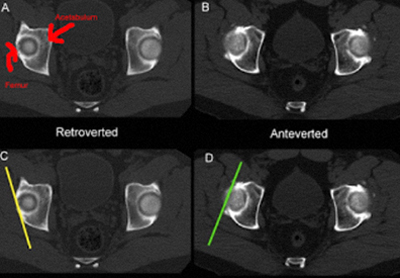

Na displasia da anca ou doença displásica da anca (DDA) o acetábulo é oblíquo, pouco profundo, estreito, lateralizado, antevertido e com deficiente cobertura anterosuperior.

O fémur tem cabeça pequena, colo curto, anteversão exagerada do colo, ângulo cervicofiafisário aumentado, desvio posterior do grande trocanter, canal femoral estreito.

D - ANTEVERSÃO EXAGERADA DO COLO DO FÉMUR